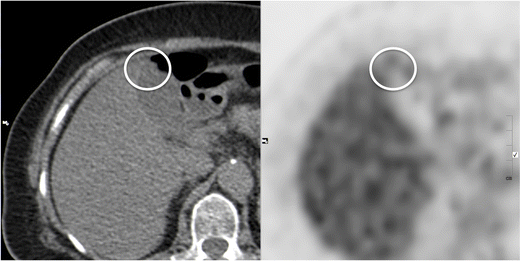

Fig. 15

Gallbladder adenomyomatosis: typical PET-CT findings. Gallbladder adenomyomatosis (circle) usually shows an F-18FDG uptake equal or lower than the adjacent liver

GA typically shows no 18 F-FDG uptake or lower uptake compared to the liver (Fig. 15). This finding is not specific for GA, but may help in excluding malignancy [33].

An acute inflammatory reaction sometimes surrounds RAS, generating an increased 18 F-FDG uptake that leads to false positive diagnosis of neoplasm [34].

PET has low spatial resolution and its accuracy in excluding early gallbladder neoplasms may be unsatisfactory in lesions measuring less then 1 cm.